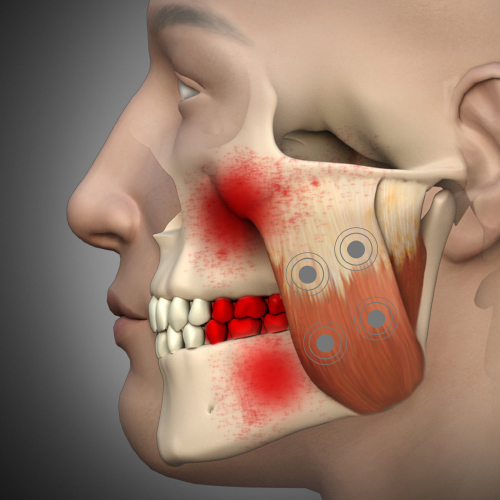

Developments in Dental Pain Management

Monday, May 17, 2021

This Compendium eBook features a continuing education (CE) article that discusses how “Frontline Temporomandibular Joint/Orofacial Pain Therapy for Every Dental Practice” is a critical topic as patients with chronic orofacial pain will often turn to their dentists first. The accompanyin...